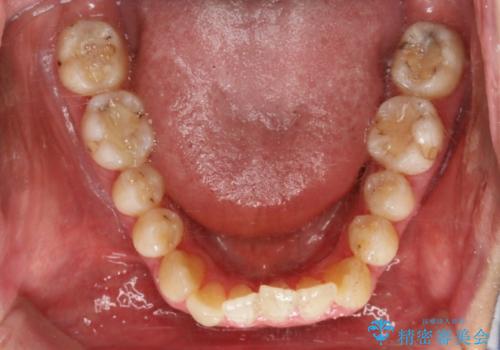

【非抜歯】八重歯を治す マウスピース矯正

- 前歯のガタつきの治療を主訴にご来院されました。

目立たない装置をとのご要望があったため、検査結果をふまえてインビザラインでの非抜歯矯正を行うこととなりました。

非抜歯での治療

抜歯をせずに歯のガタつきを治すためのスペースを作るために

①歯の遠心移動

②歯列弓の拡大

③IPR(歯を少し小さく削る)

この3つの方法を複合的に組み合わせて治療を行いました。

抜歯をせずとも笑った時の歯の見え方が劇的に変化していることが分かります。